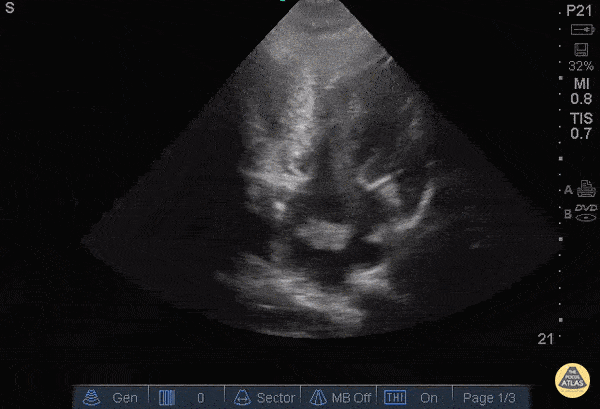

40 y/o M with atrial fibrillation, off his anticoagulation, presented with shortness of breath and was found to have a left atrial thrombus on POCUS in this apical view. Differentiating a thrombus from an atrial myxoma is difficult, but seeing the object tumble and shoot around the atrium, in the setting of afib, is both dramatic and suggestive of a thrombus. Unfortunately, timing does not differentiate the two since the average myxoma can grow at up to 0.5cm/month. The patient was admitted to the cardiac intensive care unit with full resolution of the thrombus after anticoagulation. Dr. Bryan Jarrett and Dr. John Kilpatrick - SUNY Downstate/Kings County Emergency Medicine